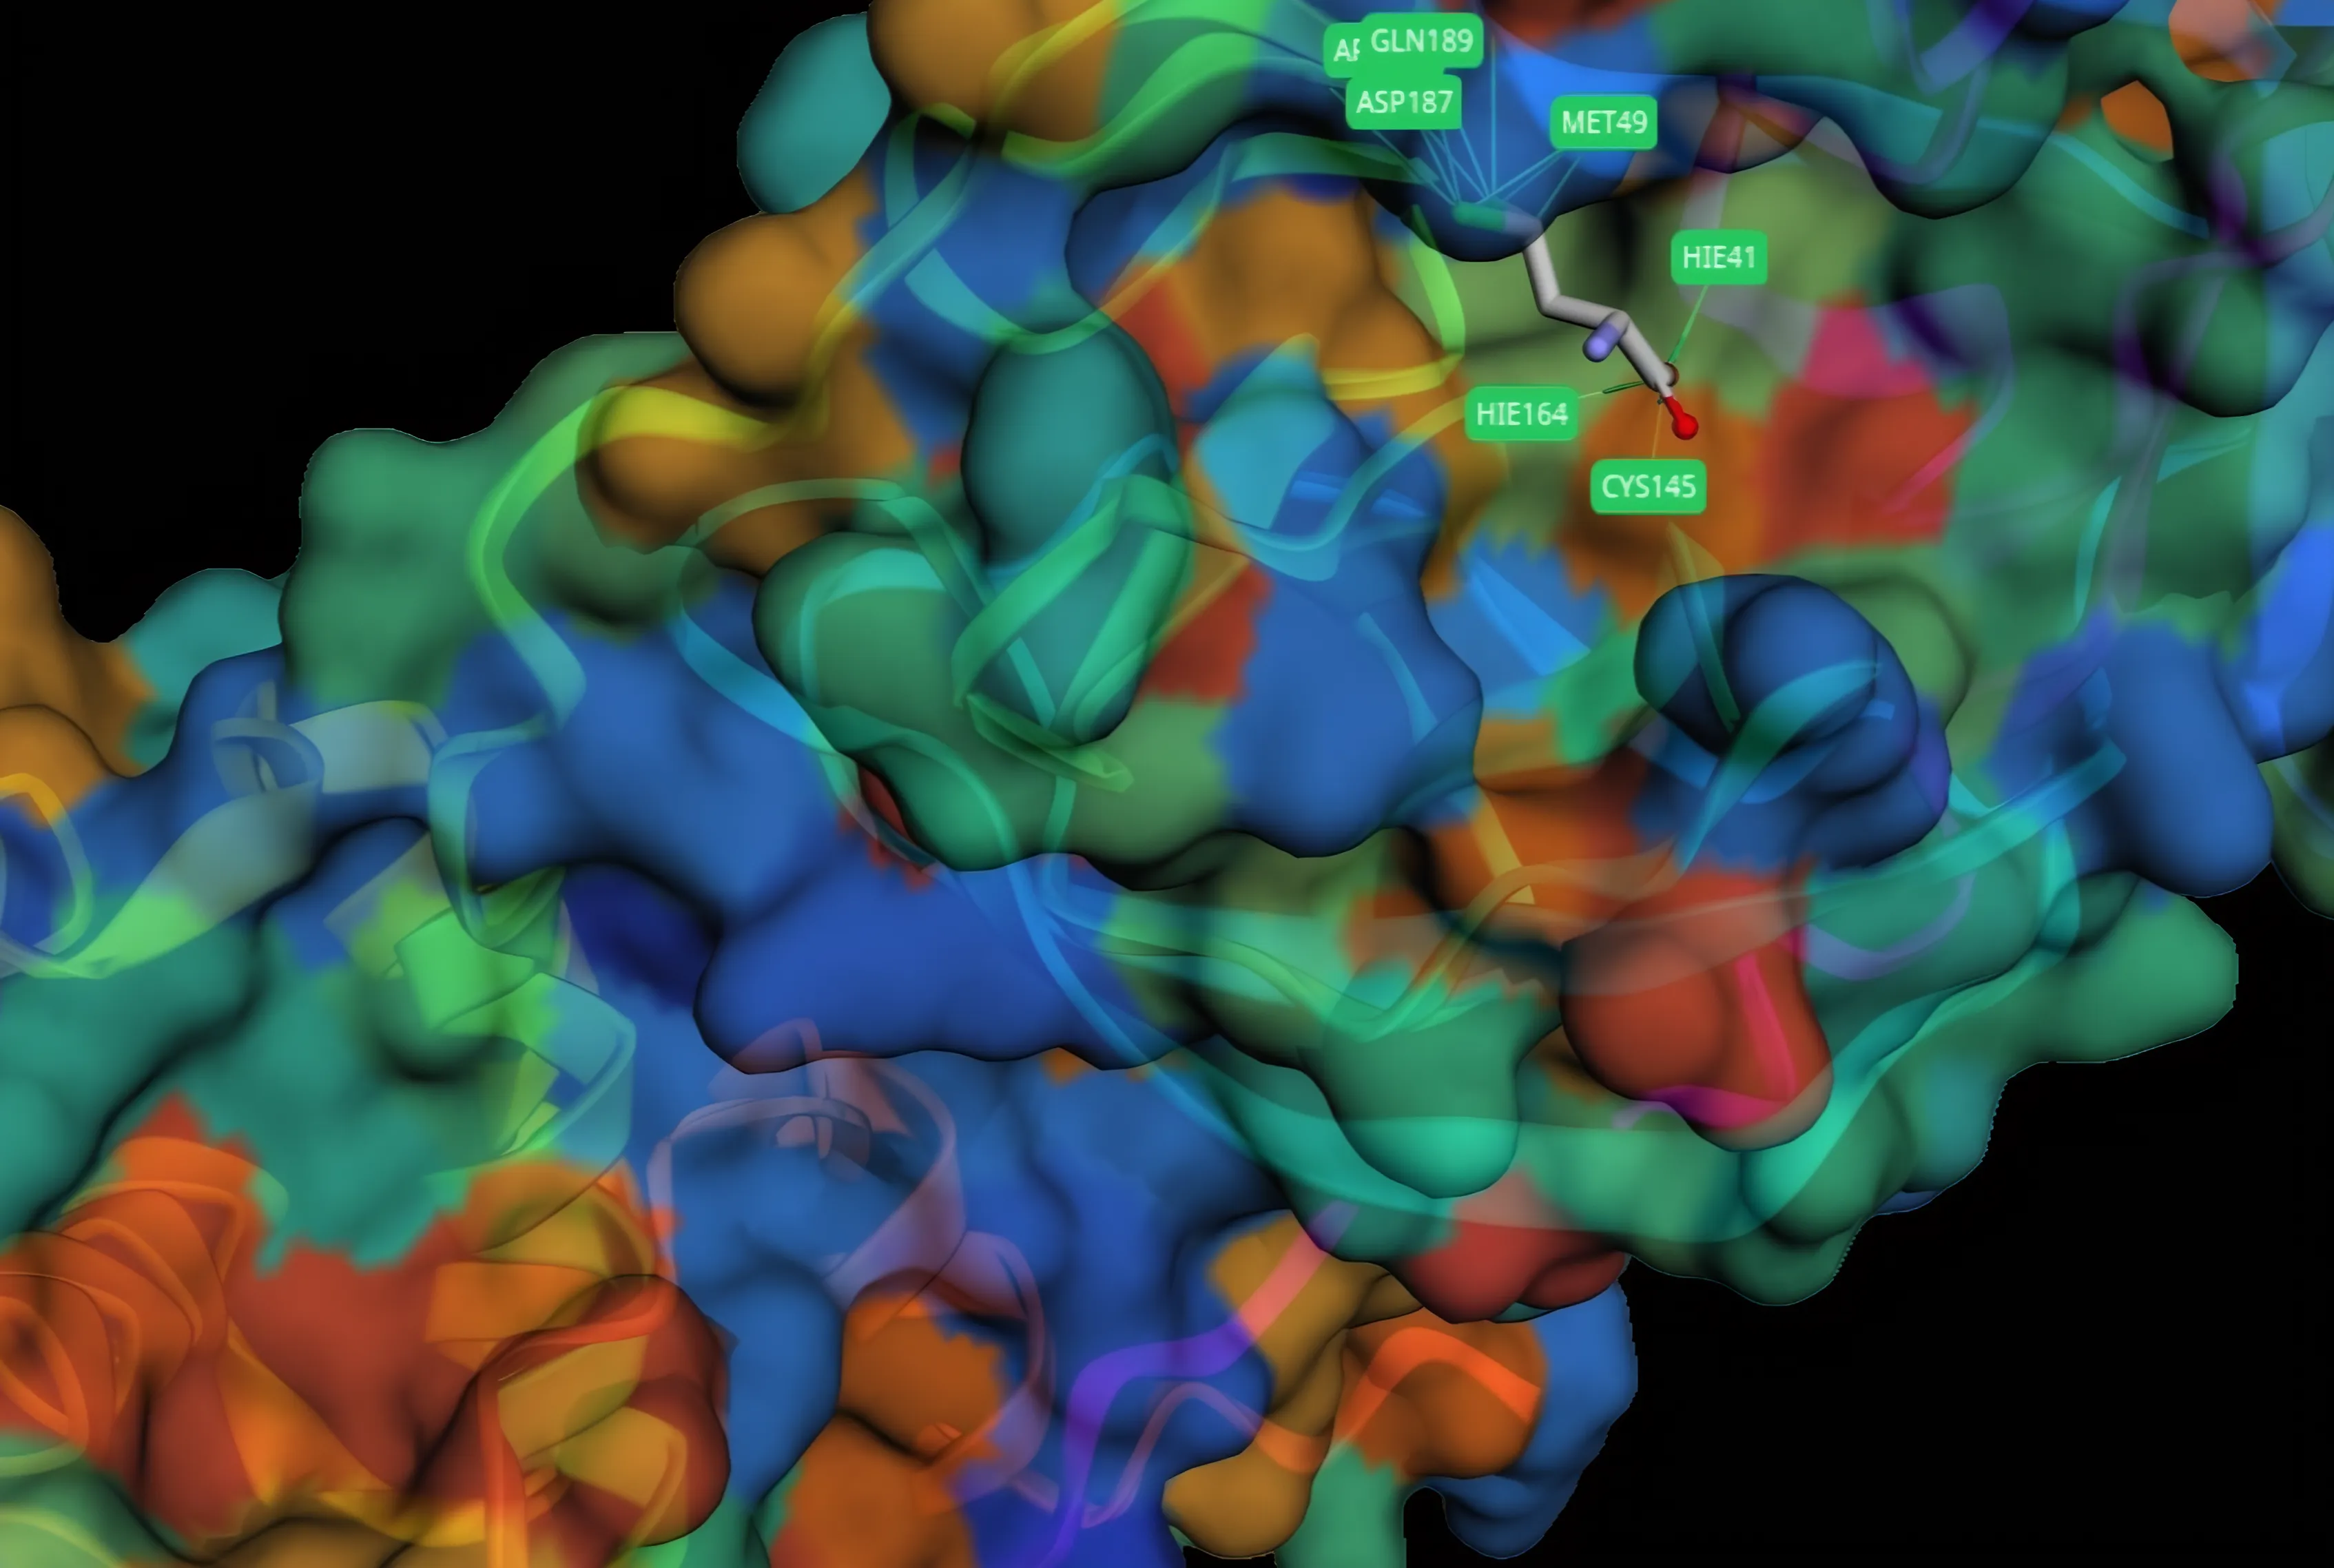

Target-Oriented Small Molecule Design

We design small molecules starting from biological targets, combining generative AI with structure-aware evaluation to rapidly explore and refine candidate chemical space.

In collaboration with academic researchers, we design AI-generated small molecules to tackle antibiotic resistance. Our platform integrates generative models, structure-based docking, and in-silico validation to accelerate early discovery and prioritize compounds with real translational potential.

We design small molecules starting from biological targets, combining generative AI with structure-aware evaluation to rapidly explore and refine candidate chemical space.